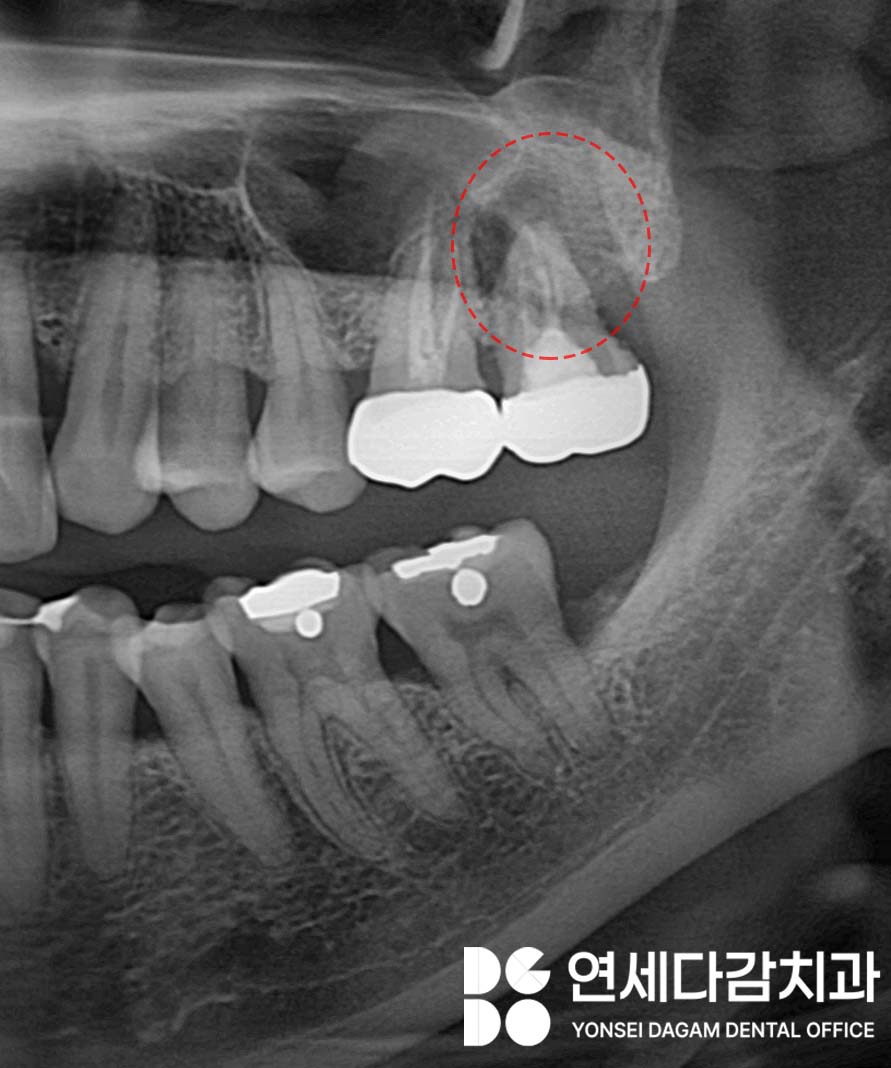

예를들어 치아 뿌리 주변에 염증이 생기면

파골세포가 과하게 활성화 되어

주변 뼈가 흡수되기 시작합니다.

치아를 지지할 조직이

파괴되었기 때문에,

점차 흔들리고

결국 발치가 불가피한 상황이

되는 일이 많습니다.